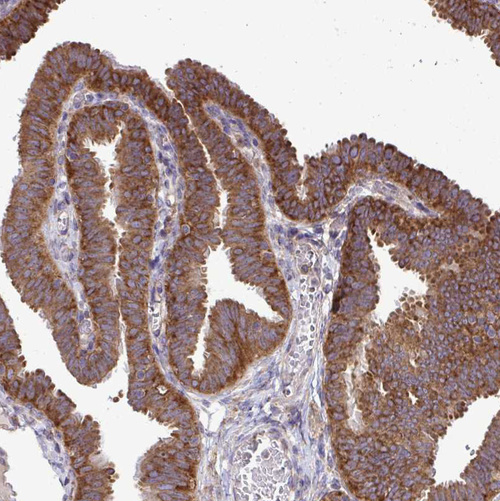

Immunohistochemical staining of human fallopian tube, liver, placenta and testis using Anti-FMR1 antibody HPA050118 (A) shows similar protein distribution across tissues to independent antibody HPA056084 (B).